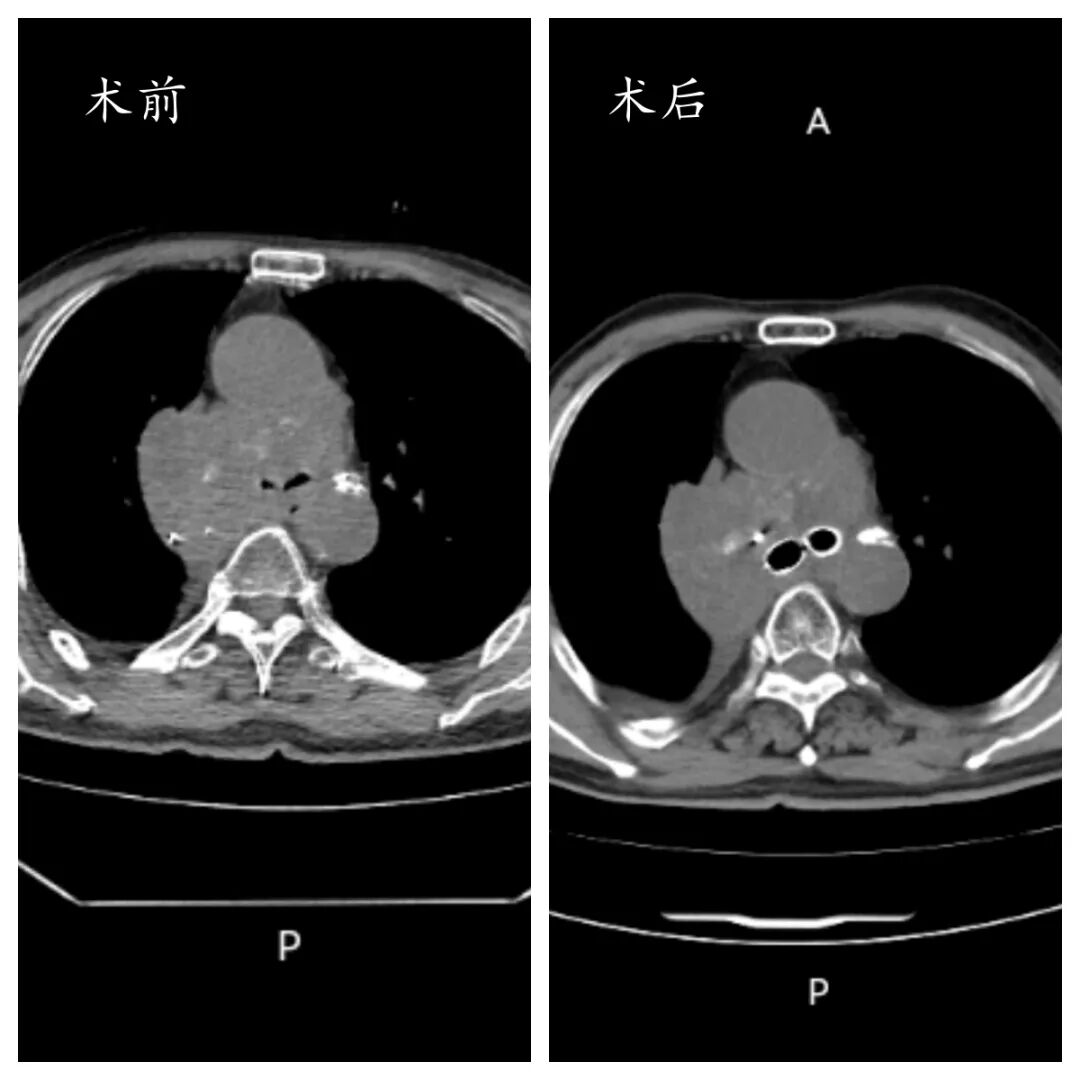

当肿瘤步步紧逼堵塞呼吸要道,当每一次吸气都成为奢望,一场与死神竞速的生死营救在我院手术室紧急上演。近日,临沂市中心医院呼吸与危重症医学科二病区介入团队凭借精湛医术,成功为一名肺癌致大气道严重梗阻患者独立实施高难度Y型支架置入术,精准打通“生命通道”,让患者重获呼吸希望。

患者秦先生(化名)因肺癌进展,出现进行性呼吸困难,病情急转直下,被紧急送往我院就诊。大气道作为人体呼吸的“核心主干道”,一旦被肿瘤严重堵塞,患者随时面临窒息风险。更为棘手的是,秦先生的肿瘤位置特殊,已累及气管隆突及双侧主支气管,形成复杂的气道梗阻,常规治疗手段难以奏效,生命危在旦夕。

综合考量后,团队一致决定为患者实施经支气管镜Y型支架置入术——这是目前治疗复杂大气道梗阻最有效的核心手段之一。“Y型支架置入对技术精度要求极高,气管隆突作为气道‘三岔路口’,支架需精准贴合病灶,既要保证固定稳定不移位,又要确保双侧主支气管完全通畅,任何细微偏差都可能导致手术失败,甚至加重病情。”邢士刚主任进一步解释道。

经过数小时的攻坚克难,Y型支架成功精准置入,完全覆盖肿瘤狭窄段,双侧主支气管瞬间恢复通畅。当监测仪器上的血氧饱和度数值稳步回升,秦先生的呼吸逐渐平稳,整个手术团队终于松了一口气。

术后,秦先生的呼吸困难症状得到显著缓解,血氧饱和度恢复至正常水平,生命体征趋于平稳。在呼吸监护室接受两天的精细化治疗与护理后,患者病情稳定,生活质量大幅提升,顺利转回普通病房继续后续治疗。